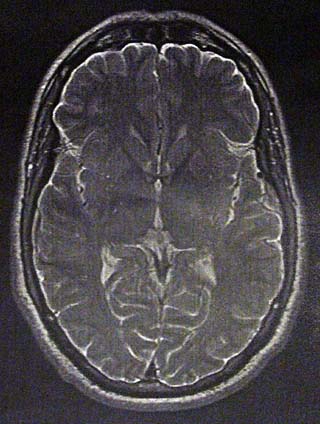

But now, scientists can use brain scans and run blood tests to detect Alzheimer’s in its earliest stage, before symptoms start to show up. The new diagnostic guidelines take that into account.